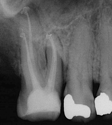

Treatment Examples

Conventional Treatment with Standard Core Restoration

Non-surgical endodontic treatment with resin core build up

All Treatment performed by Dr. Brian A. Christopherson